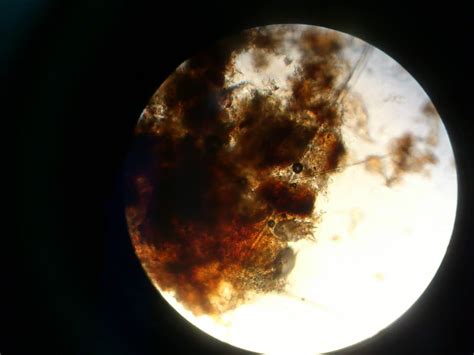

Отодектоз (ушной клещ) собак и кошек

Отодектоз

Отодектоз у кошек